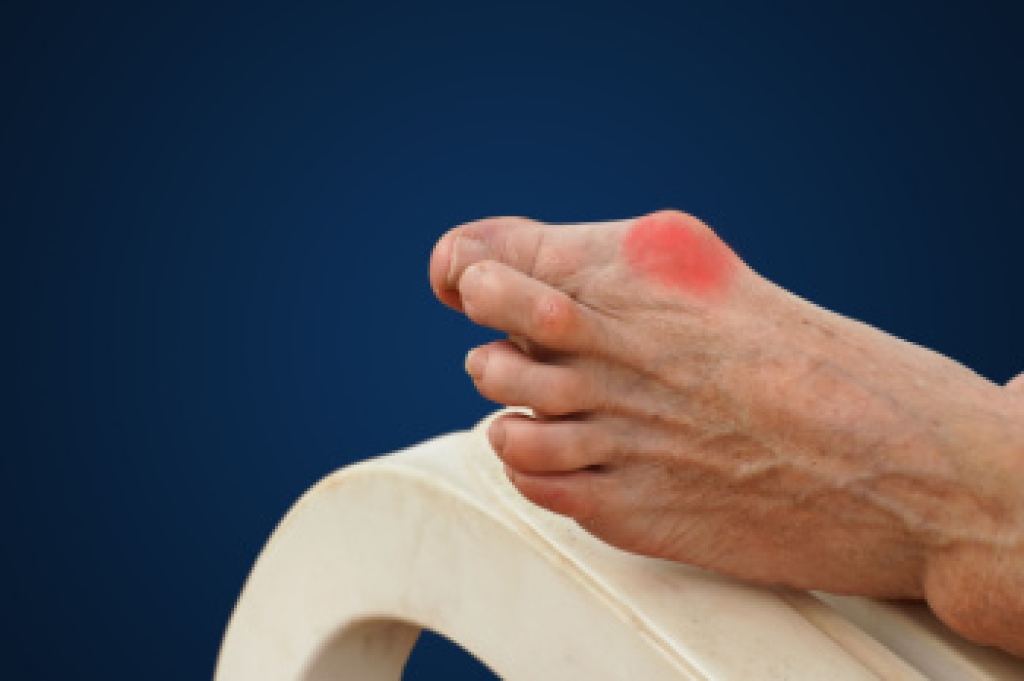

Gout is a form of inflammatory arthritis caused by the buildup of uric acid crystals in the joints, often affecting the big toe. It typically appears suddenly, with symptoms such as intense pain, swelling, redness, and warmth in the affected area. Gout attacks can be triggered by certain foods, excessive alcohol, dehydration, or medications. While lifestyle changes, such as dietary adjustments and increased hydration, can help manage mild cases, recurrent or severe attacks may require medical intervention. If you experience debilitating pain or swelling in the big toe that does not improve on its own, it is important to see a podiatrist. This type of doctor may prescribe medications to lower uric acid levels or reduce inflammation, helping to prevent future flare-ups. If you have or suspect you have gout, it is suggested you schedule an appointment with a podiatrist for a comprehensive evaluation and effective treatment options tailored to your needs.

Gout is a form of arthritis that is characterized by sudden, severe attacks of pain, redness, and tenderness in the joints. The condition usually affects the joint at the base of the big toe. A gout attack can occur at any random time, such as the middle of the night while you are asleep.

- Inflammation and Redness -Affected joints may become swollen, tender, warm and red